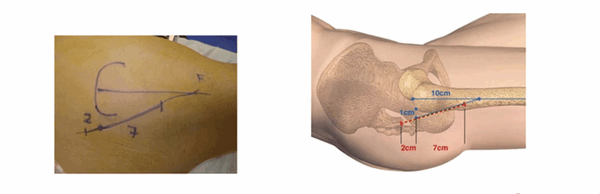

Нанесение маркеров для выполнения разреза. (Graphique de l’incision)

Нанесение ориентиров упрощает выполнение разреза. Верхний бугор большого вертела хорошо пальпируется, когда пациент находится в положении лежа на боку на плоской поверхности. От этого места наносятся две точки: первая на расстоянии 1 см располагается за бугром большого вертела, вторая — на расстоянии 10 см от вершины по оси бедренной кости. По линии, связывающей эти две точки делается разрез: 2 см ниже и 7 см выше от бугра вертела.